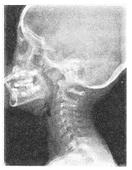

- 单项选择题 患者男性,5岁,反复呛咳,张口呼吸,有靳声,鼻腔分泌物多。X线检查如图所见,最可能的诊断是()。

A、腺样体肥大

- A